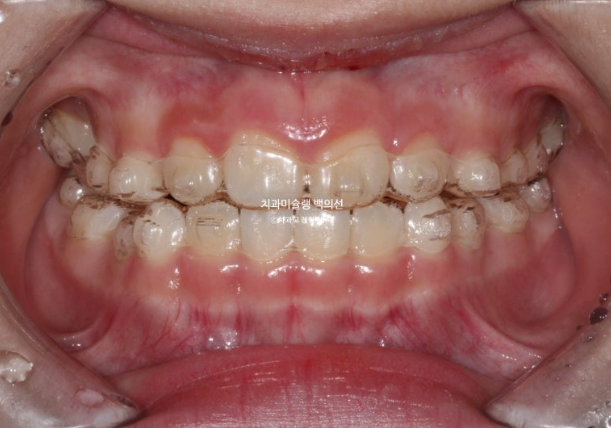

2022.10

하지만 여전히 어금니 반대교합이 남아있습니다.

유치 송곳니도 여전히 거꾸로 물려 교합간섭이 남아있습니다.

어금니 반대교합은 상악 악궁이 좁아서 생기는 문제입니다.

즉 악궁확장이 필요하고 인비절라인 퍼스트로 악궁확장을 동반하여 MA (mandible advance, 하악전진기능) 기능을 이용한 비대칭 치료가 필요합니다.